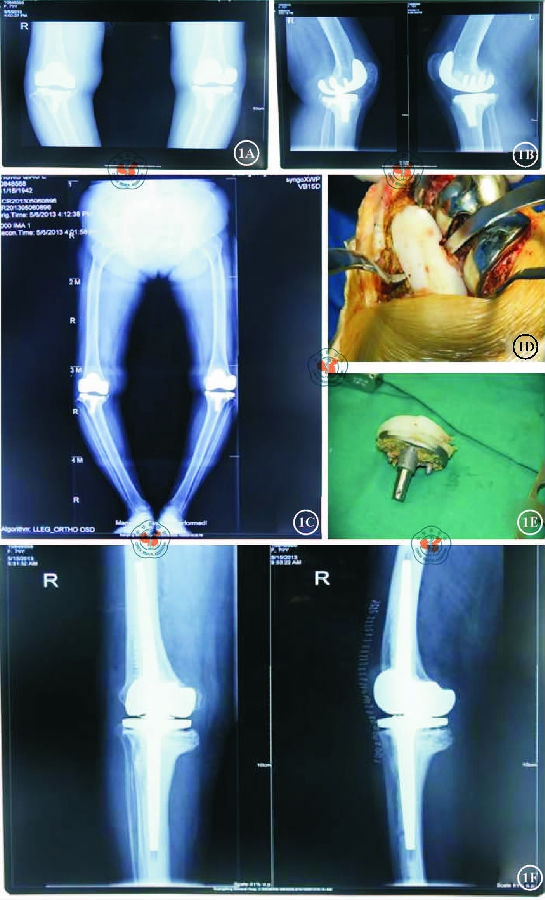

广东省人民医院骨科自2008年10月至2013年5月进行的全膝关节翻修手术,均为膝关节假体松动或者膝关节感染需行全膝关节翻修的患者,全部采用旋转铰链膝进行翻修。纳入标准:(1)膝关节屈曲畸形>15°、外翻畸形>15°内翻畸形>20°,膝关节侧副韧带严重功能障碍或断裂且无法重建及严重骨缺损者;(2)有随访记录且完整者。排除标准:侧副韧带功能完好者。本研究共10例患者(10膝)符合选择标准纳人研究,其中男4例,女6例;年龄47~77岁,平均67岁;初次置换均因膝关节骨关节炎。翻修原因:假体无菌性松动4例;TKA术后感染6例。术前7位患者膝关节内翻,内翻角度皆>20°;3位患者膝关节外翻,外翻角15°,侧副韧带严重挛缩畸形或合并严重骨缺损(图1A~1C) 0美国特种外科医院膝关节(HSS):20~52分,平均37分。按安德森骨科研究所分型系统(AORI)骨缺损分型,10例患者都属于II型非包容性骨缺损。

2.手术方法。对于无菌性假体松动的患者,本研究采用原手术切口,将髌骨翻转牵向外侧,去除原假体及骨水泥(图1D,1E),彻底清理关节内增生的纤维组织,于骨缺损处行结构性植骨或者使用金属网进行覆盖,将其变为包容性骨缺损,通过打压植骨技术进行填充,在处理完骨缺损后使用旋转铰链膝假体行一期翻修。

1.随访结果:10例均获得随访,随访时间2~57个月,平均29个月。患者翻修前HSS评分为20-52分,平均37分;术后随访时为55〜94分,平均85分。膝关节活动度术前为30°-82°,平均为65°;术后随访时为85°-100°,平均93°(图1F)。

图1女,71岁,全膝关节置换术后假体松动,使用旋转铰链膝假体进行翻修。1A术前双膝关节正位片;1B术前双膝关节侧位片;1C术前X线片可见双侧膝关节内翻畸形,双侧胫骨内侧平台骨缺损,胫骨假体下沉;1D术中见胫骨内侧平台骨缺损明显,胫骨假体下沉;1E聚乙烯衬垫磨损、分层;1F使用旋转铰链膝假体进行翻修后X线结果